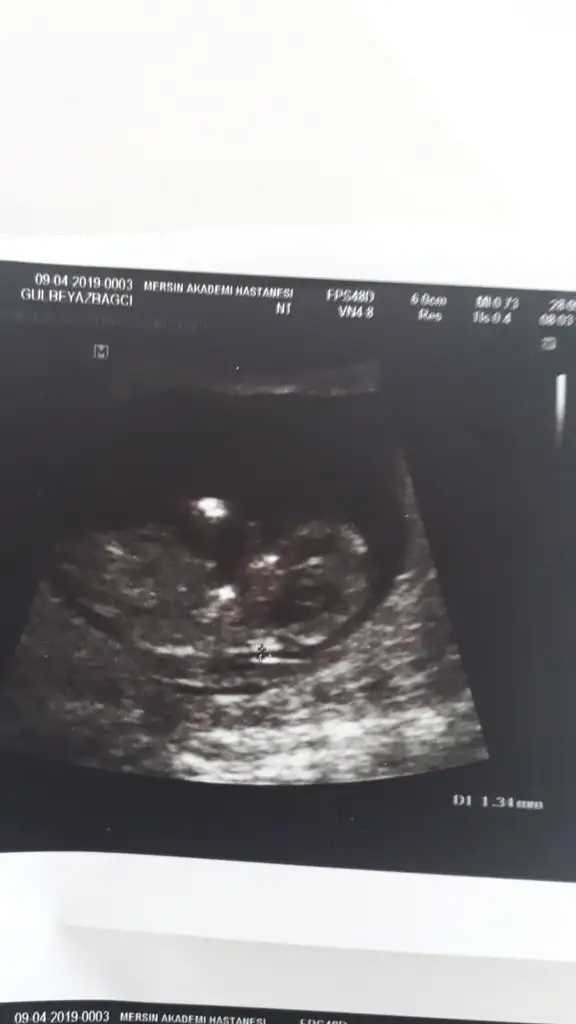

Kız bu bebiş.nub çizgisi paralelKızlar acil yardım nuba göre tahmin yapabilen varmı acaba cok merak ediyorum lütfenEki Görüntüle 2275127 Eki Görüntüle 2275128 Eki Görüntüle 2275129 Eki Görüntüle 2275127 Eki Görüntüle 2275128 Eki Görüntüle 2275129

Nuba göre kız gibi sanki. Yani yukarı doğru değilde karşıya doğru ucu.

% 90 kız bu bebiş.eminim.hatta %100 derdim ama tıpta %100 diye birsey yokturSizce kız olma oranı yüzde kaç acaba cvaplarsanız sevinirim çok

% 90 kız bu bebiş.eminim.hatta %100 derdim ama tıpta %100 diye birsey yokturkesin kız bu bebek.hayırlı olsun